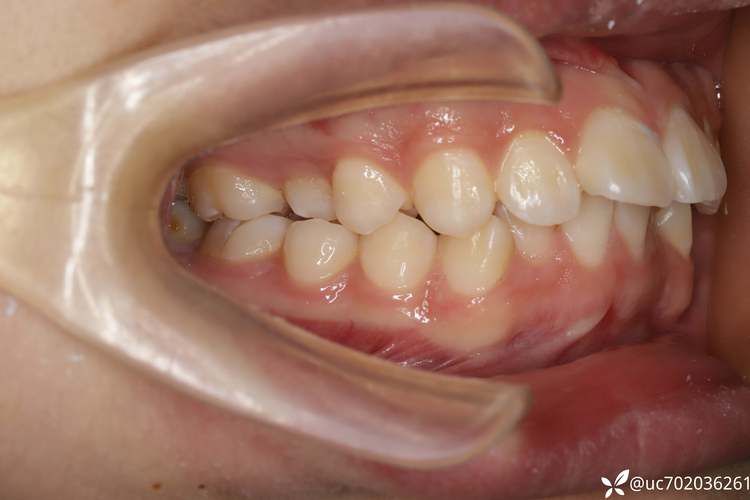

正畸结束后,种牙前需进行系统的口腔检查和评估,以确保种植安全与效果,需通过临床检查评估缺牙区牙龈厚度、邻牙松动度及咬合关系,排除牙周炎、颞下颌关节疾病等禁忌症,影像学检查必不可少,CBCT(锥形束CT)可清晰显示牙槽骨的三维形态、高度、宽度及重要解剖结构(如下牙槽神经、上颌窦位置),帮助医生判断骨量是否充足,是否需要植骨或进行上颌窦提升术,患者全身健康状况也需评估,如是否存在未控制的糖尿病、骨质疏松、长期服用抗凝药物等情况,这些可能影响骨愈合和种植体稳定性,若牙槽骨骨量不足,还需提前进行骨增量治疗,如引导骨再生术(GBR)、自体骨移植等,待骨量达到种植要求后再进行种植手术。

正畸拔牙后再种牙的治疗流程需严格遵循“先正畸、后种牙”的原则,即确保正畸治疗结束,牙齿排列整齐、咬合关系稳定后再进行种植手术,具体流程包括:①正畸结束与保持:拆除矫治器后需佩戴保持器1-2年,防止牙齿复发移位,同时观察牙槽骨的稳定情况;②种植手术:在局部麻醉下,逐级备洞后将种植体植入牙槽骨,缝合伤口,术后需注意口腔卫生,避免感染;③骨结合期:种植体植入后需等待3-6个月,与牙槽骨形成稳定的骨结合(即“骨整合”),期间避免种植体承受过大咬合力;④修复阶段:骨结合完成后,安装基台,取模制作牙冠,试戴调整后完成最终修复,恢复牙齿形态与功能。